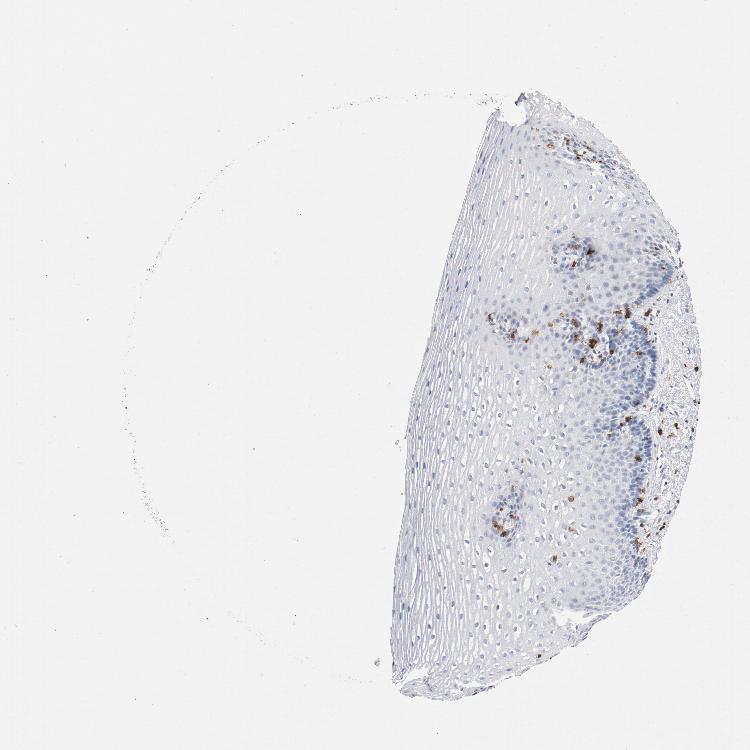

ESOPHAGUS - Antibody stainingi

Antibody staining in the annotated cell types in the current human tissue is reported as not detected, low, medium, or high, based on conventional immunohistochemistry profiling in selected tissues. This score is based on the combination of the staining intensity and fraction of stained cells.

Each image is clickable and will lead to virtual microscopy that enables deeper exploration of all samples and also displays staining intensity scores, fraction scores and subcellular localization as well as patient and tissue information for each sample.

Antibody HPA008750Antibody CAB004651

Squamous epithelial cells Not detectedNot detected